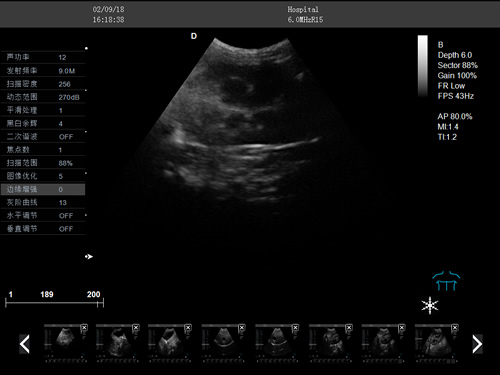

動物寵物超聲診斷儀

·牛羊馬豬犬貓及多種家禽、實驗動物、野生動物、及部分水生動物

·中小動物的肝、膽,脾、腎、膀胱、子宮、妊娠等各組織器官的檢查和病變的診斷